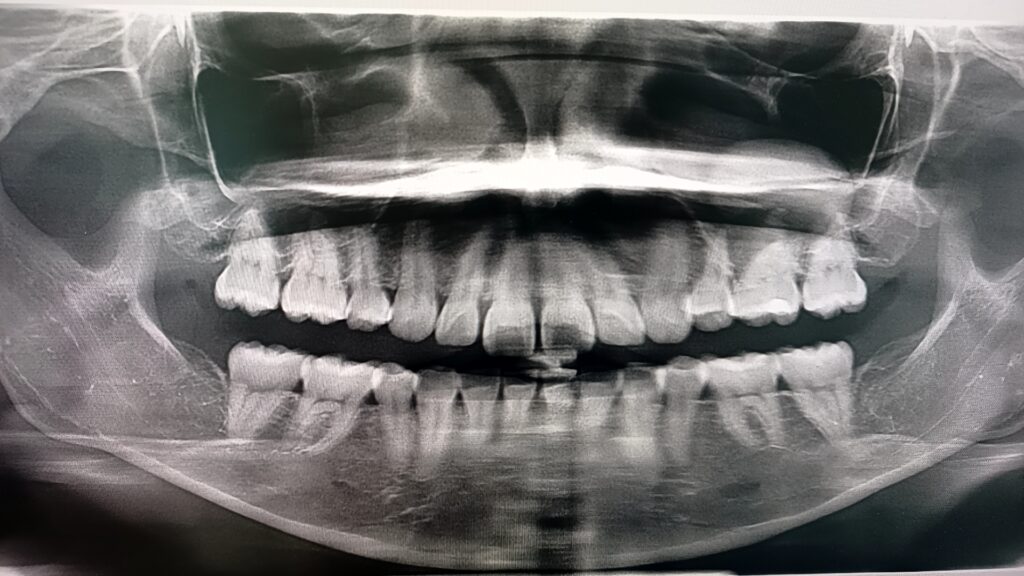

撮ってみたレントゲンですが、一見きれいなように見えるのですが、

左の上顎洞に怪しげな影が見えます。

怪しげな影とはここのところです。

しかも、隣接した歯にもわずかに影があるような。。。